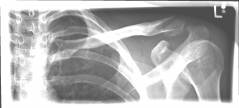

Schlüsselbein 4        Schlüsselbein 5

Pictures: Here, an angle-stable plate was used to supply the clavicle fracture near the shoulder joint. This plate makes it possible to anchor many screws in the fragment and thus obtain a good stabilization.